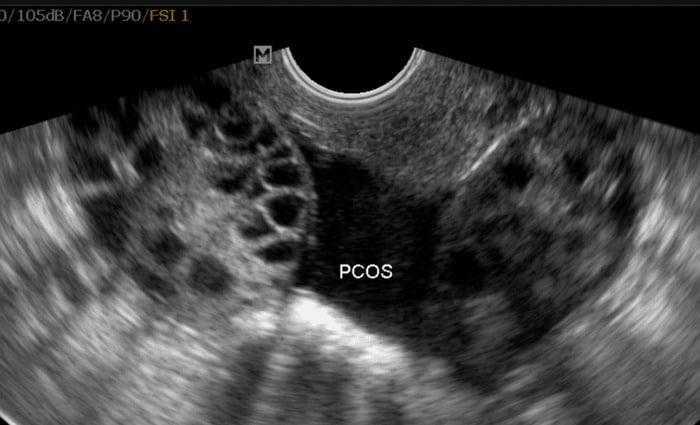

تُعد متلازمة تكيس المبايض (PCOS) واحدة من أشهر الحالات المؤثرة على الصحة الإنجابية لدى النساء، حيث تمثل السبب الرئيسي للعقم في النساء في جميع أنحاء العالم.

الجدير بالذكر أن متلازمة تكيس المبايض هي عبارة عن مجموعة من الأعراض المتعلقة بالاختلال الهرموني الذي لا يوجد له تعريف عالمي ثابت؛ ومن ضمن هذه الأعراض: زيادة الوزن، وظهور التكيسات الكبيرة على سطح المبيض، وصعوبة التبويض، وزيادة شعر الوجه مع ظهور حب الشباب، وأيضاً الإصابة بالاكتئاب.